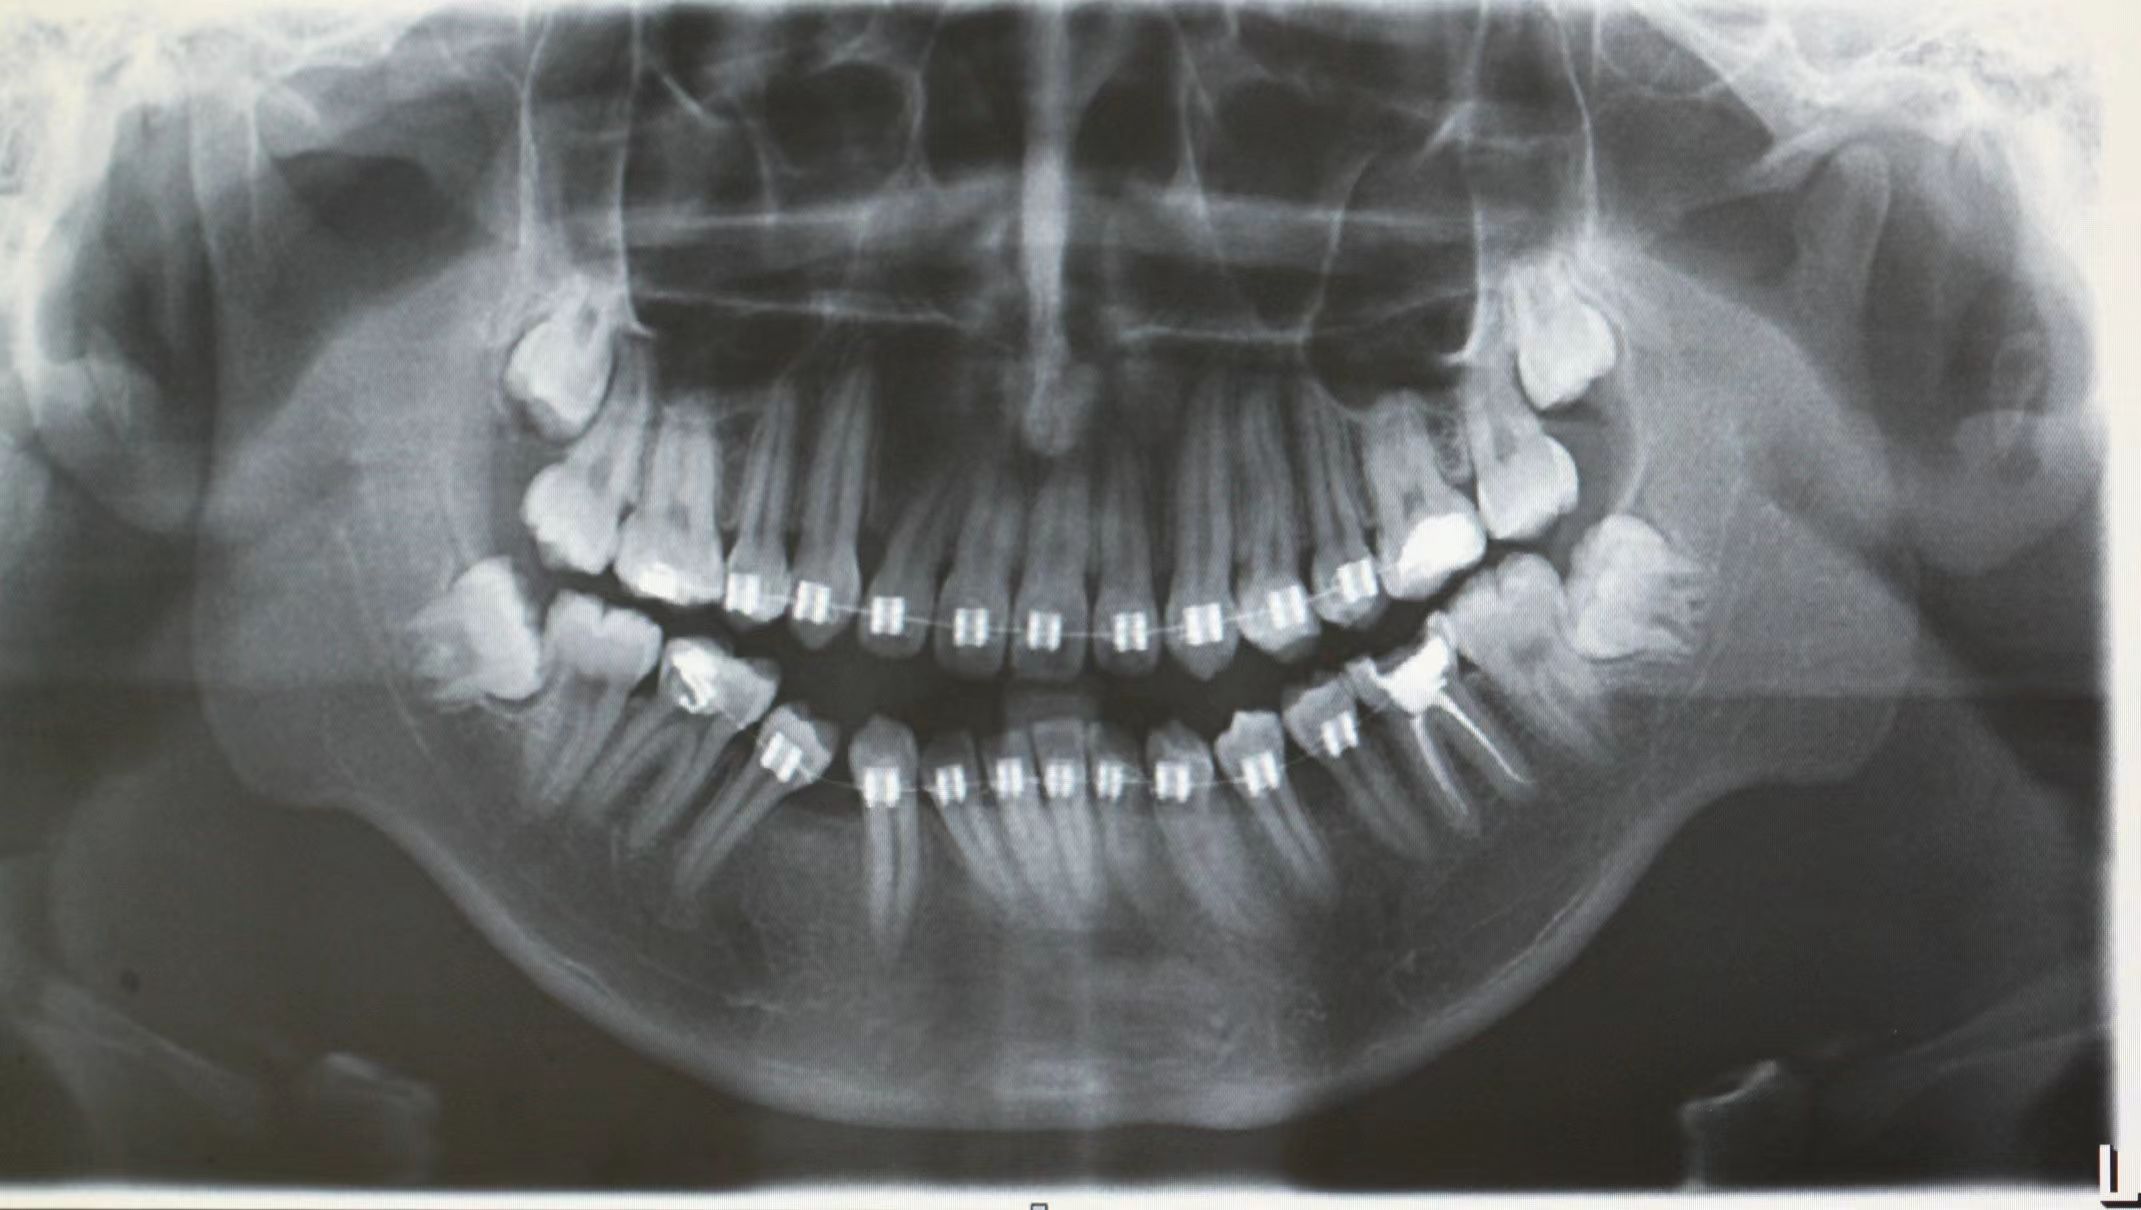

情况:不接受外科手术,在当地做了1年半的矫治,遇到困难无法进行。由外地正畸同行推荐来上海寻求非手术矫治的二手病例。武广增老师接收时的错合畸形情况,呈现严重的骨性反合偏合及侧方开合(图1-图10)。由于推荐其去口腔医院接受正颌外科手术遭到拒绝,武广增老师通过专业的检查、分析,制定一套详细的治疗计划,采用了磨牙推进器技术、武式辅弓技术等特色正畸手段获得明显效果(图2-1~图2-9)。治疗结束后也拍摄了相关照片(图3-1~图3-9)。

矫治前

图2